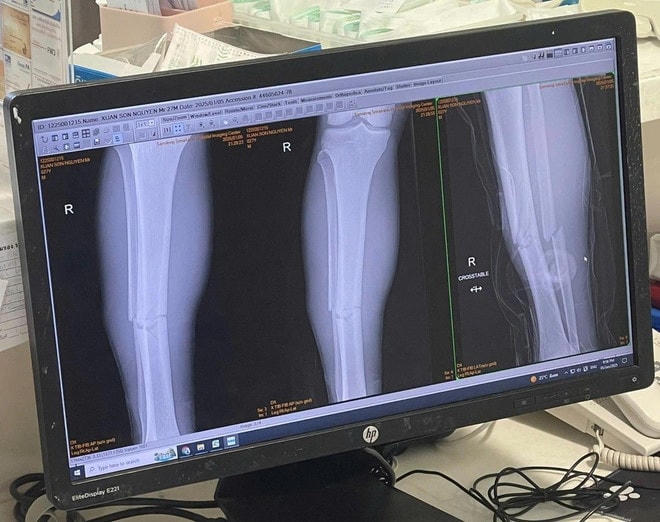

Theo kết quả chụp chiếu, tiền đạo Xuân Son gãy hai xương ở chân phải, sẽ phải nghỉ thi đấu trong nhiều tháng.

Theo kết quả chụp chiếu tại bệnh viện, Xuân Son gãy hai xương ở ống chân phải, cần nhiều thời gian để điều trị và hồi phục. Hiện chưa rõ thời điểm tiền đạo số 12 của ĐT Việt Nam có thể tái xuất.